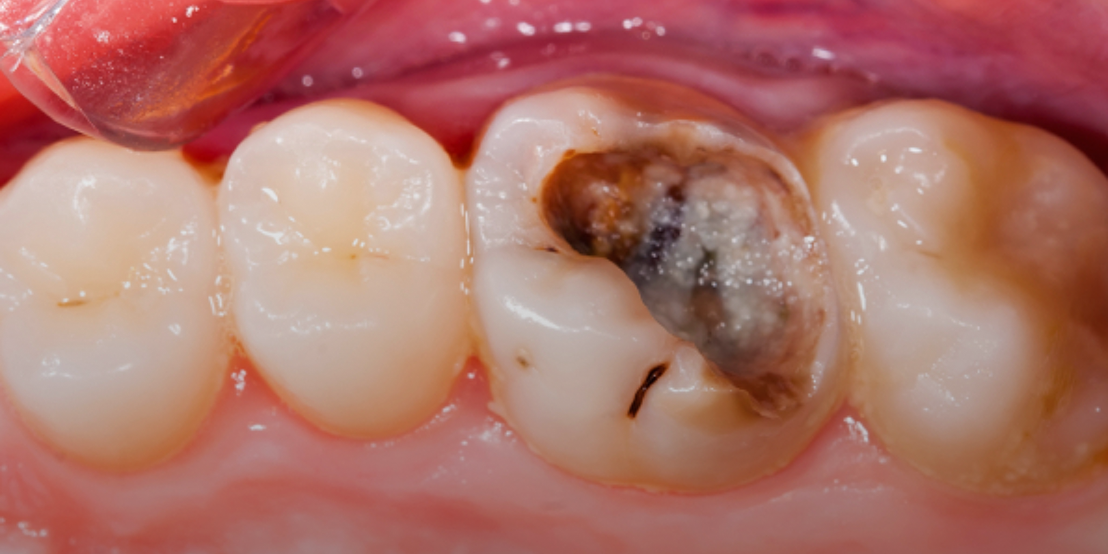

Root canal therapy removes infected pulp while preserving the natural tooth, offering pain relief and preventing further issues. At our clinic, we perform root canal Dubai procedures using advanced tools for accurate cleaning and long-term results.

In cases of severe pain, we offer emergency root canal Dubai services to treat infections promptly. Our team follows proven root canal treatment steps in Dubai to ensure your comfort and a smooth recovery. A crown is placed afterward to restore function and protect your natural smile.